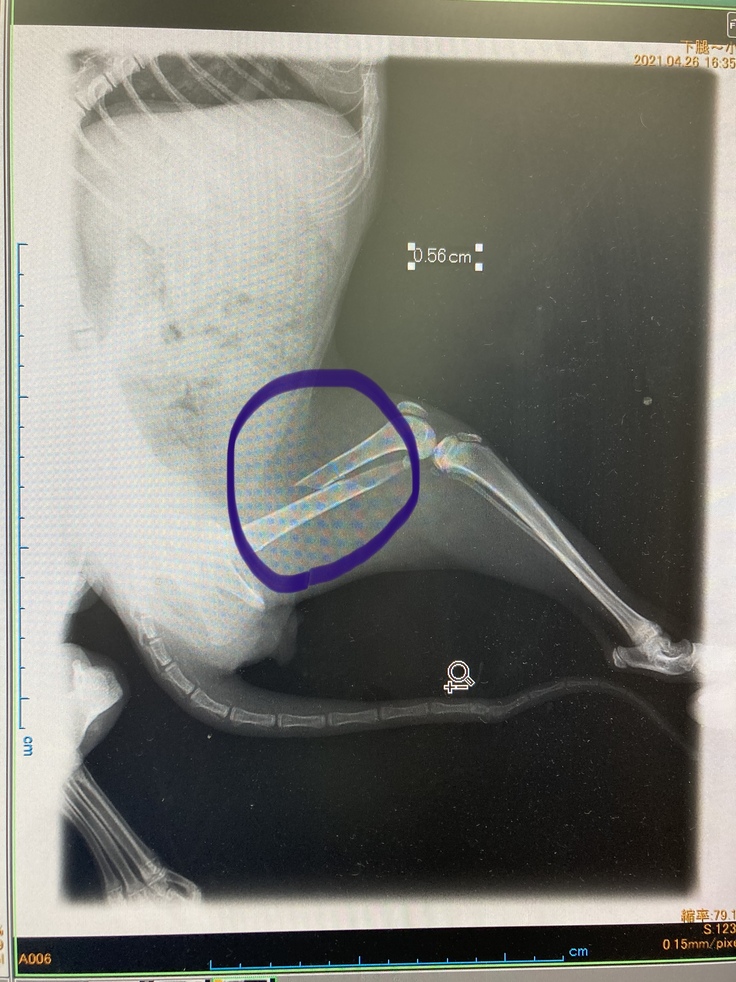

骨盤と左大腿骨の2箇所を骨折しており、すぐにでも手術が必要な状態でした。

4/28 金属プレートで骨を固定する手術をしました。幸いにも排便に支障がある程の状況迄至らず無事に手術は成功しそのまま安静の為入院となりました。

・治療・手術内容:骨盤、左大腿骨骨折によるボルト固定手術・入院・抜糸・完治後ボルト摘出

骨盤と左足骨折の手術